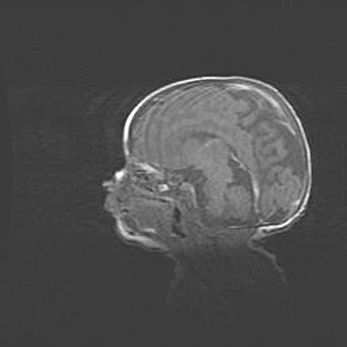

Аномалия Денди-Уокера. Признаки гипоплазии мозолистого тела.

Возраст: 5 месяцев 3 дня

Вес: 5550 г

Пол: мужской

Окружность головы: 39 см

Срок гестации: 40 недель

Аномалия Денди-Уокера – это порок развития головного мозга, для которого характерна триада симптомов: гипотрофия или аплазия червя мозжечка и/или полушарий мозжечка, расширение четвёртого желудочка с формированием ликворной кисты задней черепной ямки, гипертензионная гидроцефалия различной степени.

Гипоплазия мозолистого тела относится к дефектам внутриутробного этапа развития мозговой ткани, возникающим в процессе закладки структур головного мозга, что происходит на начальных этапах развития эмбриона.